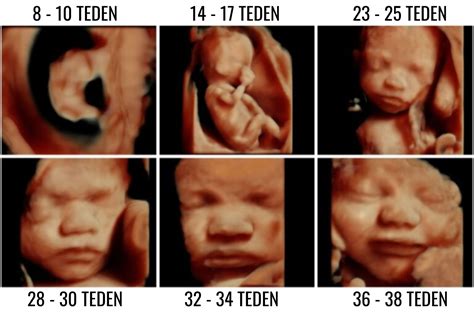

V sedmem in osmem tednu se nadaljuje hiter razvoj možganov in obraza zarodka. Nastanejo dlani in prsti na rokah in nogah. Plod v sedmem tednu meri od temena do trtice 7-9 mm. V osmem tednu se začne premikati, čeprav teh gibov mati še ne zazna. Razvije se nosna kost, spolne žleze pa se usmerjajo v razvoj jajčnikov ali testisov.

9. in 10. teden: Rast in napredek

V devetem tednu plod meri približno 1,5 do 2 cm in tehta okoli 3 grame. V desetem tednu srce bije s hitrostjo približno 160 utripov na minuto. Večina sklepov okončin je že izoblikovanih, plodov rep pa izgine. Plod meri približno 3 cm in tehta 4-5 gramov.

13. in 14. teden: Nadaljnje oblikovanje

V 13. tednu se na prstih začnejo razvijati prstni odtisi. Razvile so se zasnove za vseh 20 mlečnih zob, trebušna slinavka pa prične izločati inzulin. Na ultrazvočnem pregledu je v tem času že mogoče določiti spol otroka. Plod meri približno 7 cm in tehta okoli 20 gramov. Opazni so dihalni gibi, plod požira plodovnico in izloča urin. Koža je poraščena z mehkimi lanugo dlačicami.

15. in 16. teden: Gibanje in čutila

V 15. tednu plod meri približno 10 cm in tehta okoli 70 gramov. Lahko že sesa palec. Kosti skeleta se krepijo, razvoj mišic se nadaljuje. Oči so zaprte, vendar postanejo dovzetne za svetlobo, razvija se sluh. Od 16. tedna dalje je možna amniocenteza, invazivna diagnostična metoda. Gibi okončin postajajo vse bolj usklajeni.

31. in 32. teden: Pridobivanje teže in razvoj pljuč

Plod intenzivno pridobiva težo, koža postaja bolj napeta in rožnata. V 32. tednu tehta približno 1700 g. Zenice že lahko reagirajo na svetlobo. Pljuča so še edini življenjsko pomemben organ, ki ni dovolj razvit za samostojno delovanje zunaj maternice.

33. in 34. teden: Hitro pridobivanje teže in zrelost posteljice

Plod zdaj tehta že okoli 2000 g in meri več kot 40 cm v dolžino. Še vedno je v obdobju hitrega pridobivanja teže, zaradi razvoja možganov raste tudi glava. Pljuča zdaj že izločajo surfaktant, ki omogoča, da se zračni mehurčki napolnijo z zrakom. Količina plodovnice je v tem času največja. Posteljica je zrela.